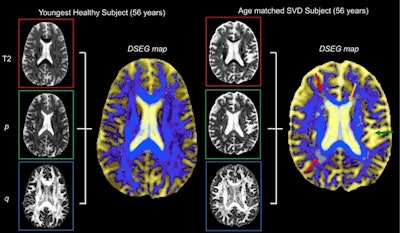

Diffusion tensor image segmentation color maps of the brain from healthy subject and age-matched SVD subject. By overlaying T2, p and q images, brain sensitive alterations in brain microstructure are visible. Red arrows indicate white matter hypersensitivities; orange arrow shows corpus callosum; green arrow shows the greater volume of cerebrospinal fluid space. © 2017 The Authors (CC BY-NC-ND 4.0).

The DSEG technique enables imaging of gray matter, white matter, cerebrospinal fluid, and white matter hypersensitivities, which when combined to create a DSEG Θ angular score can quantify brain damage effectively. The authors note a limitation of this study is the lack of consideration for the spatial location of SVD-related pathology.

Common imaging techniques for diagnosing and monitoring SVD only use a single marker, which does not always correlate strongly with disease progression and cognitive decline. The DSEG technique acquires scores by comparing SVD patients' brain scans with those of age-matched healthy controls. This process accurately depicts microstructure changes within the brain.